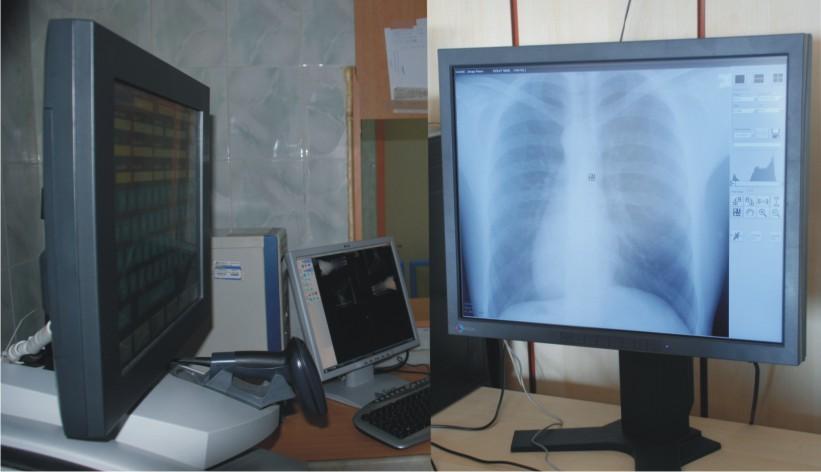

Görüntülerin daha net izlenebilmesi için Medikal Monitörler kullanılıyor.

Work Station ile birlikte yüksek çözünürlükteki görüntülerin net görüntülenebilmesi, tanı ve teşhisle-rin sağlıklı yapılabilmesi için tasarlanmış Medikal Monitörler kullanılıyor.

Görüntülerin işlenebilmesi için Work Station kullanılıyor.

Work Station, hızlı grafik işlemcilere sahip gelişmiş donanımdan oluşuyor. Work Station'a yüksek çözünürlük ve boyuttaki görüntülerin hızlı bir şekilde işlenebilmesi için gereksinim duyuluyor.